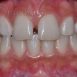

Interdisciplinary Treatment of Patients with Deep Overbite and Parafunctional Activity

Bruxism is defined as parafunctional grinding of teeth and due to the excessive wear of the posterior teeth, patients with long-standing bruxism often have pathological deep overbite. For many decades, treatment of bruxism and deep overbite was focused on reshaping the bite for achieving an occlusion free of deviations. Despite large efforts, the management of bruxism and subsequent deepening overbite was not obtained.